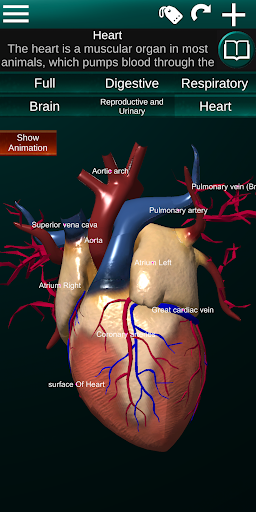

* Heart, which includes the atria, ventricles, aorta and an animation of this organ.